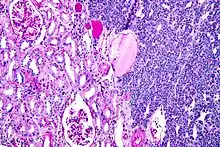

| Micrograph of a metanephric adenoma with structures reminiscent of those seen in papillary renal cell carcinoma. H&E stain. | |

Metanephric adenoma (MA) is a rare, benign tumour of the kidney, that can have a microscopic appearance similar to a nephroblastoma (Wilms tumours),[1] or a papillary renal cell carcinoma.

Metanephric adenoma is diagnosed histologically. The tumours can be located at upper pole, lower pole and mid-hilar region of the kidney; they are well circumscribed but unencapsulated, tan pink, with possible cystic and hemorrhagic foci. They show a uniform architecture of closely packed acinar or tubular structures of mature and bland appearance with scanty interposed stroma.[3][4][5][6][7] Cells are small with dark staining nuclei and inconspicuous nucleoli. Blastema is absent whereas calcospherites may be present. Glomeruloid figures are a striking finding, reminiscent of early fetal metenephric tissue. The lumen of the acini may contain otherwise epithelial infoldings or fibrillary material but it is quite often empty. Mitoses are conspicuously absent.[3][4][5][6][7] In the series reported by Jones et al. tumour cells were reactive for Leu7 in 3 cases of 5, to vimentine in 4 of 6, to cytocheratin in 2 of 6, to epithelial membrane antigen in 1 of 6 cases and muscle specific antigen in 1 of 6.[5] Olgac et al. found that intense and diffuse immunoreactivity for alpha-methylacyl-CoA racemase (AMACR) is useful in differentiating renal cell carcinoma from MA but a panel including AMACR, CK7 and CD57 is better in this differential diagnosis.[8] Differential diagnosis may be quite difficult indeed as exemplified by the three malignancies initially diagnosed as MA that later metastasized, in the report by Pins et al.[9]